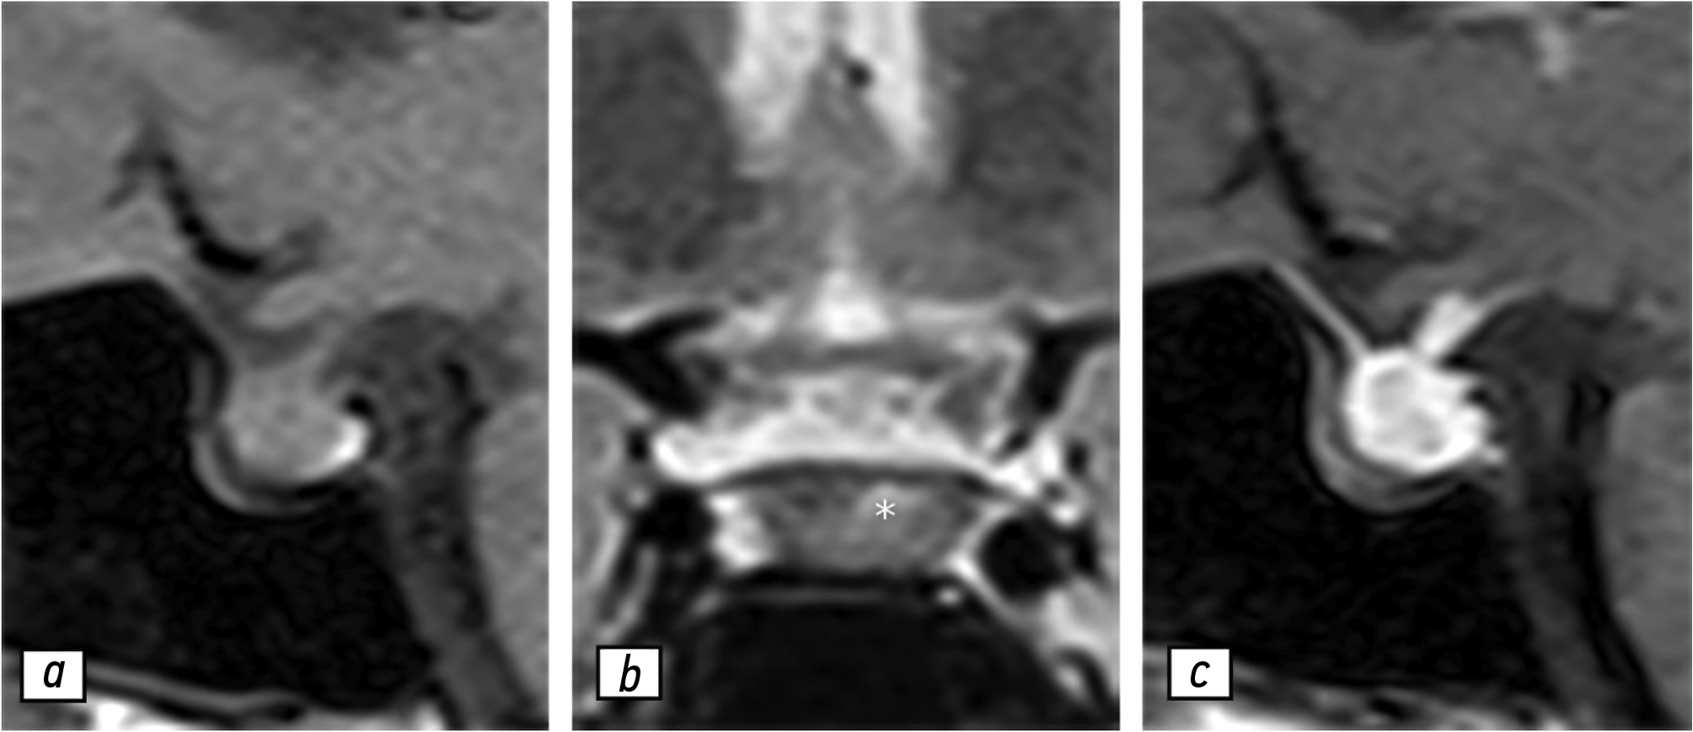

Согласно данным МРТ гипофиза с контрастированием (рис. 1), гипофиз имел слегка гетерогенную структуру и нормальные размеры:

- в сагиттальной плоскости — 1,3 см;

- в вертикальной плоскости — 1 см;

- во фронтальной плоскости — 2 см.

Рис. 1. Результаты магнитно-резонансной томографии гипофиза, 02.05.2020: a — T1-взвешенное изображение в сагиттальной проекции; b — T2-взвешенное изображение в коронарной проекции; с — T1-взвешенное изображение в сагиттальной проекции с контрастированием. Гипофиз (звёздочка) не увеличен и имеет слегка гетерогенную структуру.

Отмечено незначительное отклонение ножки гипофиза влево. После введения гадолиний-содержащего контрастного вещества в центре вещества гипофиза обнаружено незначительное неравномерное усиление магнитно-резонансного сигнала. Несмотря на то что клиникорадиологическая картина не демонстрировала наличие гипофизита, рекомендовано проведение контрольной МРТ по причине гетерогенности структуры гипофиза.